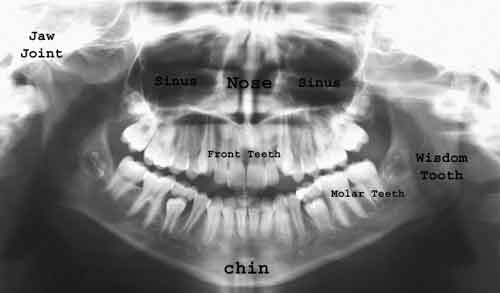

حبيبتي لازم تروحي على دكتور ويعمل لك اشعه للفك كامل اسمها بانوراما متل الي بصوره

واشعه تانيه اسمها سيفالومتريك cephalometric x ray

متل الي بصوره

وبعدها الطبيب يحدد اذا متل مابتحكي عندك مشكله بالفك بهي الحاله ممكن تحتاجي تدخل جراحي عشان الدكتور الجراح يرجع لك الفك واقصد بالدكتور الجراح الي هو استشاري جراحه الوجه والفكين

وبهيك يصير اسمها

الجراحة التقويمية Orthodontic Surgery